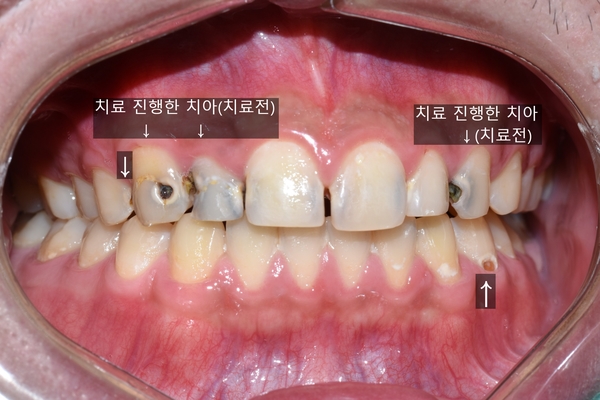

앞에서 봤을 때도 충치가 심해 보였고, 특히 앞니 충치가 눈에 띄게 보였습니다.

그리하여 진짜 충치가 심각하게 심한 어금니 몇 개와 앞니 몇개를 치료 하였습니다.

몇 개 치아 치료 후 (환자분이 일부만 치료하길 원함)

전과 후 (보이는 곳만 표시, 어금니도 일부 치료하셨습니다)

비용문제와 여러 문제로 일부만 치료하였기 때문에